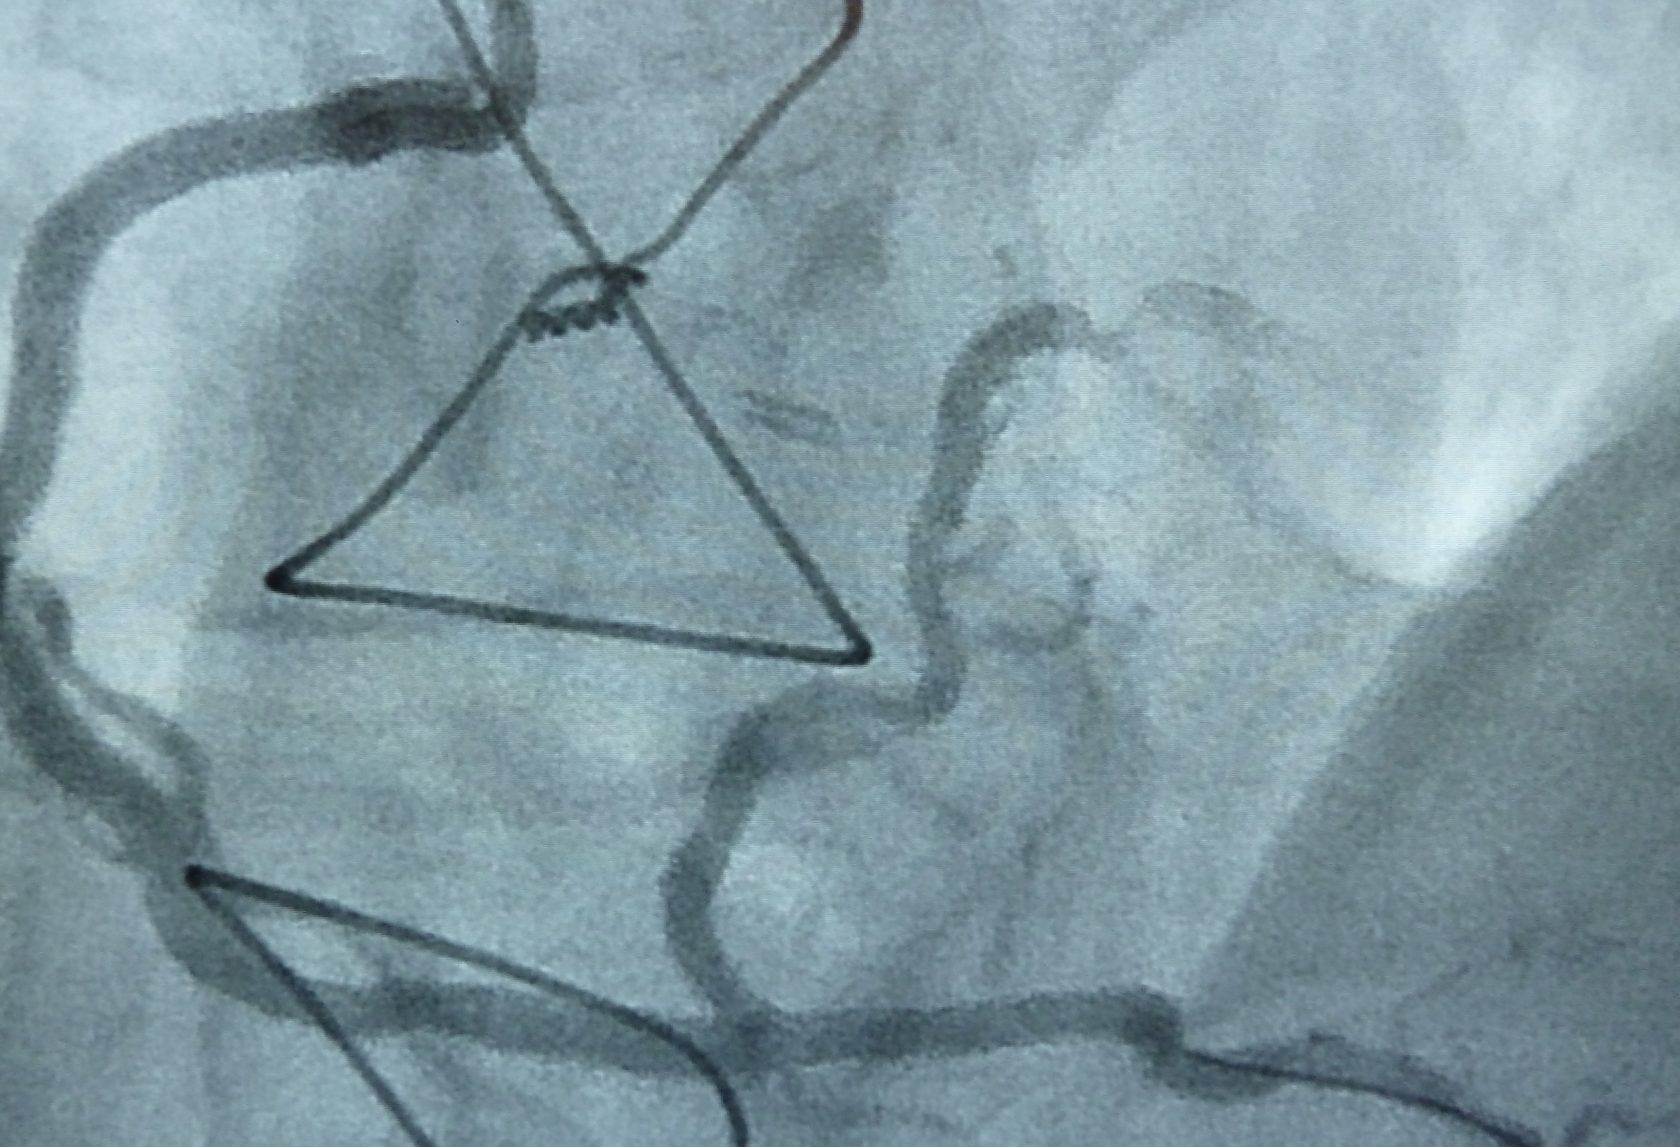

Grundsätzlich ist das Vorgehen analog zur Herzkatheteruntersuchung. Vorbereitung und Einführung des Katheters geschehen wie dort geschildert. Es werden zunächst Medikamente zur Gerinnungshemmung und zur Erweiterung der Kranzarterien gespritzt. Durch den in der Kranzarterie liegenden Katheter wird nach Darstellung der Kranzarterie ein sehr weicher, flexibler Führungsdraht über die Kranzgefäßverengung vorgeführt. Über diesen als Leitschiene wird dann der eigentliche Ballonkatheter nachgeführt und der Ballon in der Verengung unter hohem Druck aufgeweitet. Sollte dies nicht gelingen, kann die Verengung auch mit einer speziellen Fräse abgetragen werden (Rotablation).

In den meisten Fällen ist auf dem Ballon direkt ein Stent (Gefäßstütze aus metallischem Maschenwerk) aufgesetzt, der durch die Dehnung in die Gefäßwand gepresst wird. Der Druck im Ballon wird entlastet und dieser entfernt. Der Stent bleibt lebenslang im Gefäß und wächst innerhalb Monaten ein. Nach Kontrolle durch Darstellung des Gefäßes wird der Katheter und die Schleuse entfernt.

Ist die genaue Einschätzung von Verengungen an den Herzkranzarterien schwierig, können wir in ausgewählten Fällen auch mit einem intravaskulären Druckdraht (FFR) oder Ultraschall (IVUS) die Gefäße untersuchen.